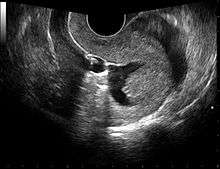

![]() Left hydrosalpinx on gyn. ultrasonography | |

Gynecologic ultrasonography or gynecologic sonography refers to the application of medical ultrasonography to the female pelvic organs (specifically the uterus, the ovaries, and the Fallopian tubes) as well as the bladder, the adnexa, and the Pouch of Douglas. The procedure may lead to other medically relevant findings in the pelvis.